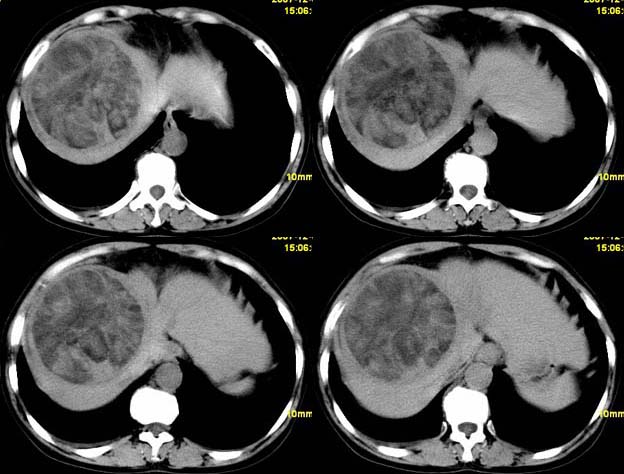

增强